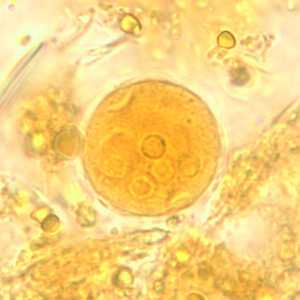

E. coli cysts in concentrated wet mounts.

Figure A: Cyst of E. coli in a unstained concentrated wet mount. Six nuclei are visible in this focal plane.